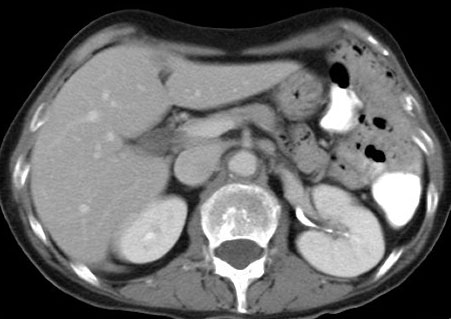

CASO 1: Paciente de 58 años que se realiza TC de abdomen tras historia de dolor abdominal y hematuria microscópica. Refiere pérdida de peso en las últimas semanas.

Estamos ante una afectación bilateral del espacio perirrenal, más evidente en el lado derecho, por masas de densidad de partes blandas en un paciente con numerosas adenopatías retroperitoneales. Estaría indicado realizar una biopsia, ya que el diagnóstico principal orienta hacia un síndrome linfoproliferativo, espcialmente linfoma no Hodgkin tipo B.

2. LINFOMA.

El linfoma renal presenta una gran variedad de manifestaciones. Entre un 3 y un 8 % de linfomas estudiados por TAC tienen afectación renal o perirrenal, más frecuentemente el tipo no Hodgkin.

Patrones de afectación del linfoma renal:

- Multiples masas renales en el riñón (+frecuente)

- Lesión solitaria.

- Adenopatías retroperitoneales con extensión directa a riñón y EPR (nuestro caso de hoy).

- Afectación del espacio perirrenal aislada.

- Infiltración difusa de uno o ambos riñones.

En el caso de que el linfoma afecte al EPR, se ve como una masa homogénea que ocupa este espacio y que desplaza el riñón hacia adelante, ocupando a menudo también el espacio pararrenal anterior. La afectación aislada del EPR por el linfoma es poco frecuente (<10%), es más común la extensión directa desde las adenopatías o grandes conglomerados/masas retroperitoneales (+frec) o la extensión desde el riñón.